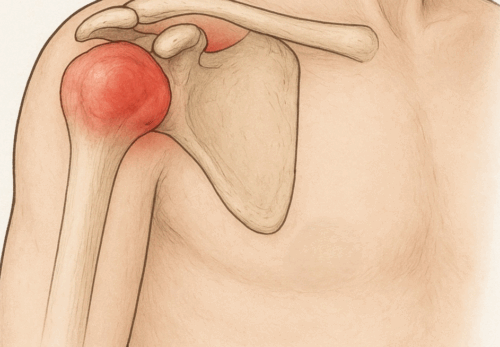

膝のお皿(膝蓋骨)のすぐ下、スネの骨(脛骨)にある

出っ張り部分が強く引っ張られることで炎症が起こり、

膝の下が腫れて痛みを感じます。特に走る・跳ぶ動作を

特に太ももの前の筋肉(大腿四頭筋)が硬くなると、膝の下にある脛骨粗面が強く引っ張られ、炎症や痛みの原因になります。

- 炎症による膝周囲の痛みをやわらげる

- 硬くなった大腿四頭筋やふくらはぎを緩めて、膝への負担を減らす